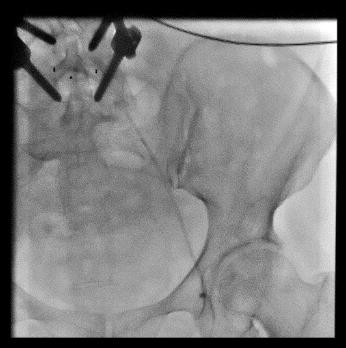

髂股静脉血栓大部分溶解,显示左髂静脉受压情况(Cockett综合征),见图5

图5